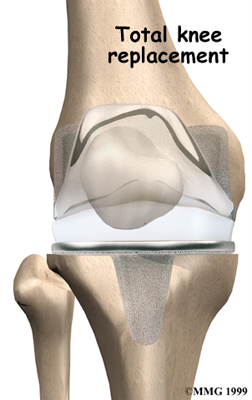

Artificial Knee Replacement

An artificial knee replacement is the ultimate solution for advanced knee OA.

Surgeons prefer not to put a new knee joint in patients younger than 60. This is because younger patients are generally more active and might put too much stress on the joint, causing it to loosen or even crack. A revision surgery to replace a damaged prosthesis is harder to do, has more possible complications, and is usually less successful than a first-time joint replacement surgery.

Related Document: FYZICAL NW St. Augustine's Guide to Artificial Joint Replacement of the Knee